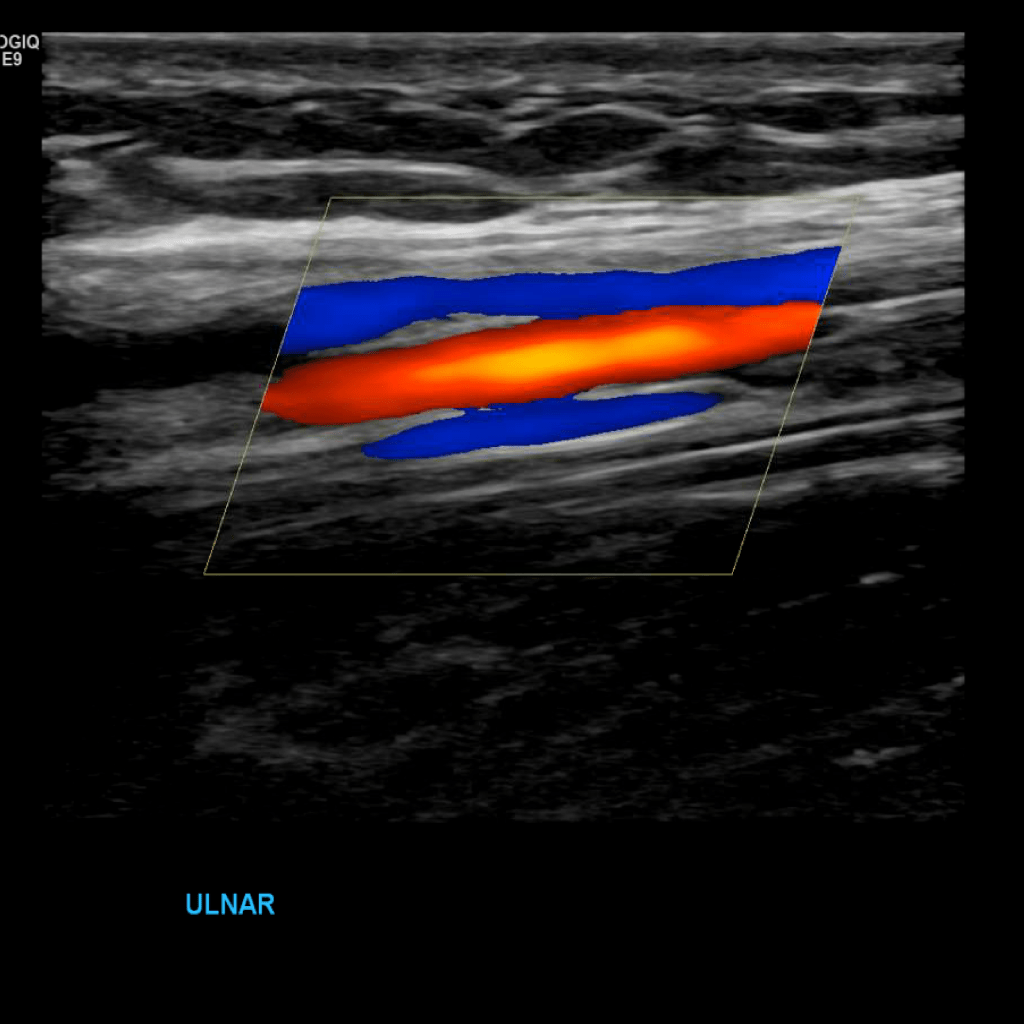

Scan the ulnar veins in grey scale, compression, color doppler and spectral doppler